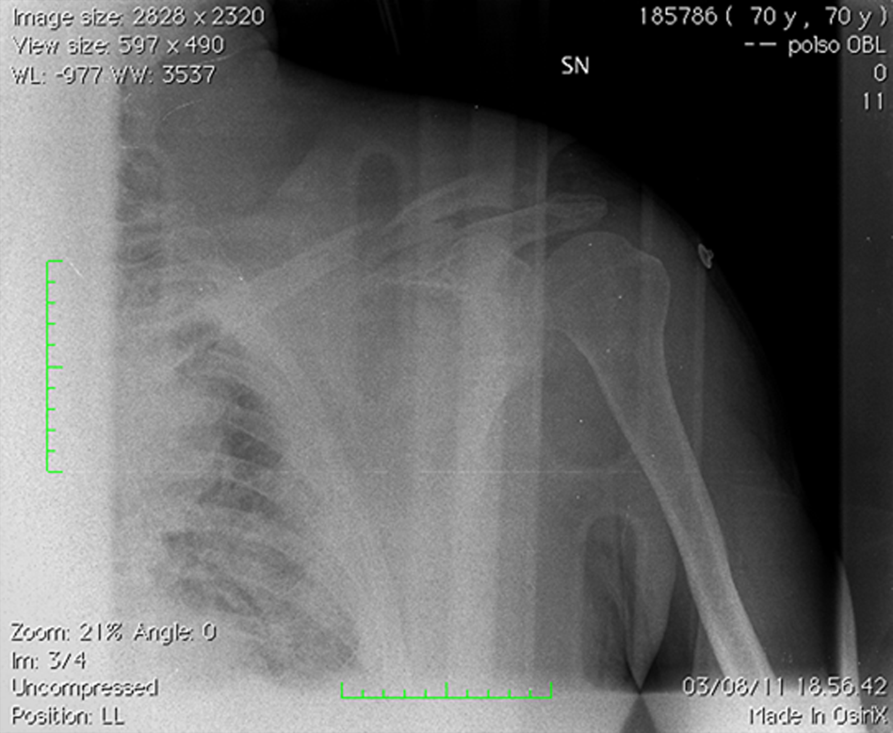

ECG: Sinus Tachycardia. - XR

-

XR shows left midshaft clavicular fracture.

No pneumothorax was present on XR. - Further imaging: US / Angiogram